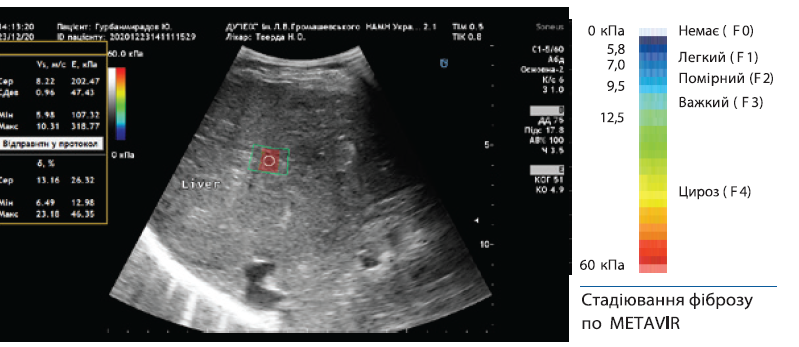

Еластометрія — як термін має на увазі отримання цифрових значень жорсткості в кПа які застосовуються при оцінці стадії фіброзу печінки по METAVIR.

Стадії фіброзу:

F0 — відсутність фіброзу,

F1 — розширення портальних трактів без формування септ,  F2 — портальний фіброз в поєднанні з одиничними септами,  F3 — портальний фіброз в поєднанні з множинними септами, F4 — цироз печінки.

Зсувнохвильова еластографія — виконується за допомогою мультипараметричного ультразвукового апарату (Soneus P 7, Cannon, Siemens тощо).